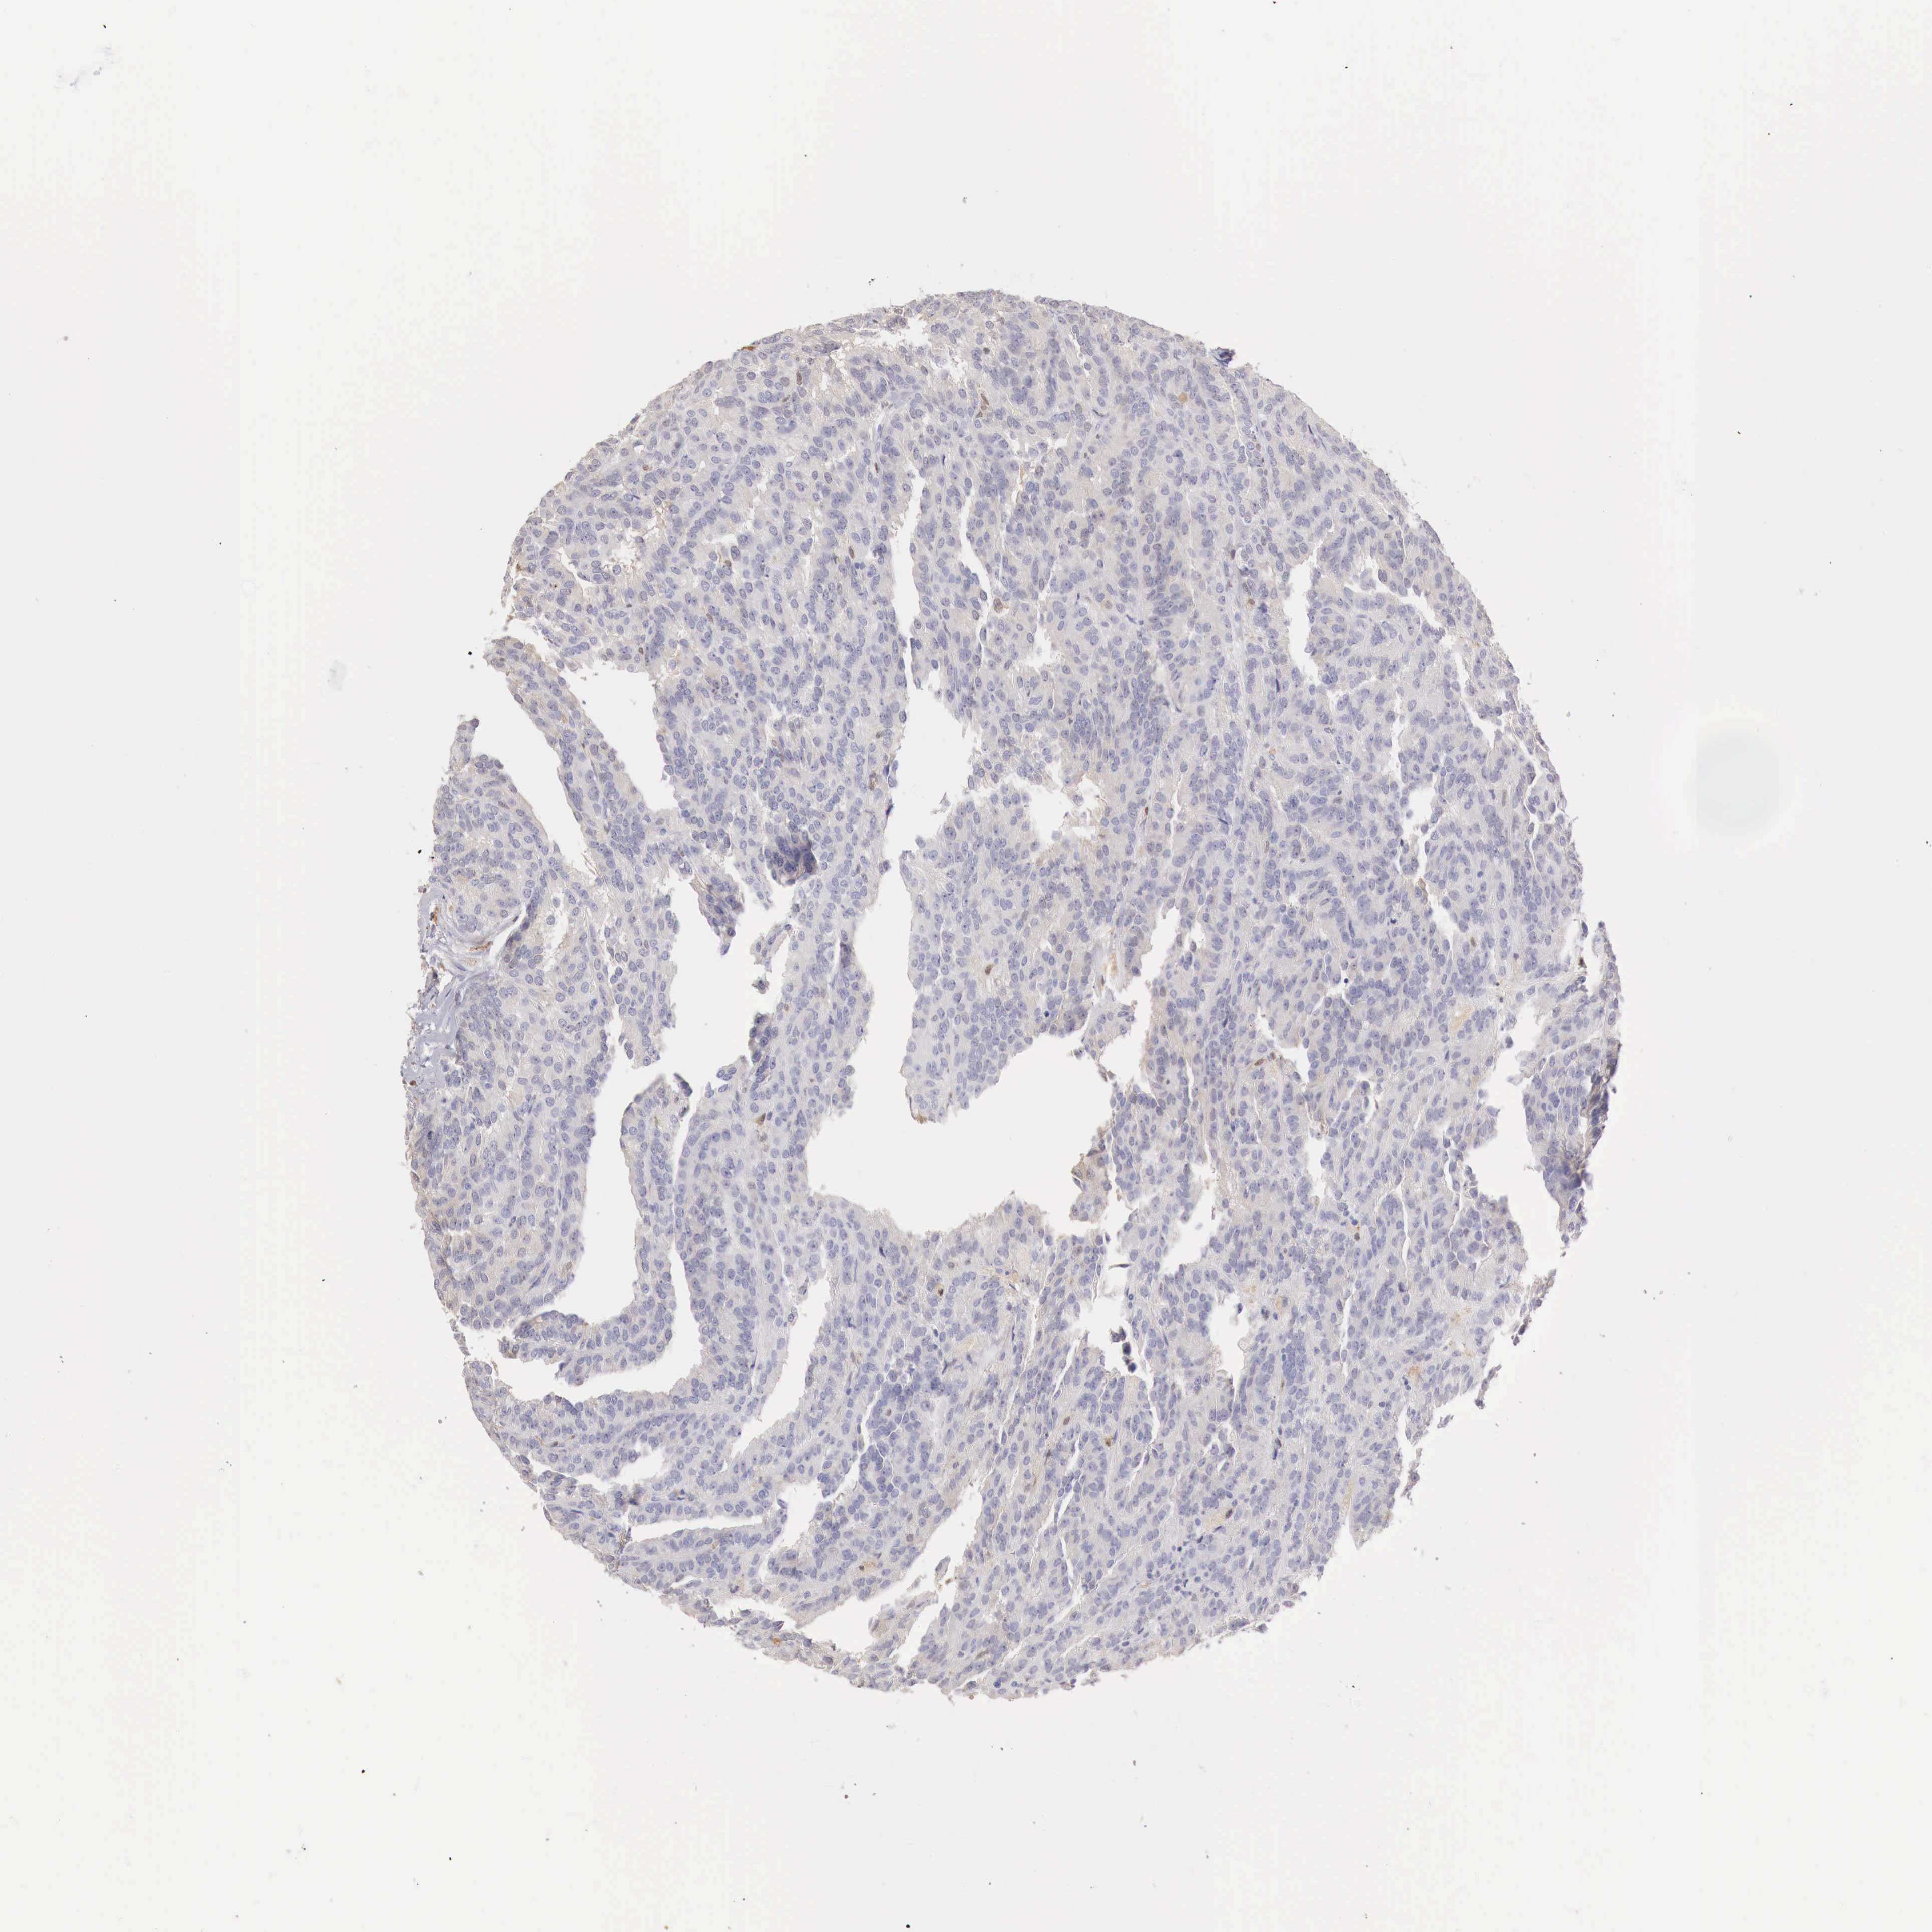

KIDNEY RENAL CLEAR CELL CARCINOMA (VALIDATION) - Interactive survival scatter ploti

The Survival Scatter plot shows the clinical status (i.e. dead or alive) for all individuals in the patient cohort, based on the same data that underlies the corresponding Kaplan-Meier plots. Patients that are alive at last time for follow-up are shown in blue and patients who have died during the study are shown in red.

The x-axis shows the expression levels (FPKM) of the investigated gene in the tumor tissue at the time of diagnosis. The y-axis shows the follow-up time after diagnosis (years). Both axes are complimented with kernel density curves demonstrating the data density over the axes. The top density plot shows the expression levels (FPKM) distribution among dead (red) and alive patients (blue). The right density plot shows the data density of the survived years of dead patients with high and low expression levels respectively, stratified using the cutoff indicated by the vertical dashed line through the Survival Scatter plot. This cutoff is automatically defined based on the FPKM cutoff that minimizes the p-score. The cutoff can be changed by dragging the vertical line or by entering a cutoff value in the square labeled "Current cut-off".

Under the Survival Scatter plot the p-score landscape (black curve; left axis) is shown together with dead median separation (red curve; right axis). Dead median separation is the difference in median mRNA expression between patients who have died with high and low expression, respectively. It is calculated as follows: median FPKM expression of dead patients with high expression - median FPKM expression of dead patients with low expression. This is intended to aid the user in visually exploring custom cutoffs and the associated p-scores and dead median separation.

Individual patient data is displayed and can be filtered by clicking on one or more of the category buttons on the top of the page. Categories describing expression level and patient information include: high, low, alive, dead, female, male and tumor stages. The scale of the x-axis can be toggled between linear and log-scale by clicking on the "x log" button. Mouse-over function shows TCGA ID, patient information and mRNA expression (FPKM) for each patient.

& Survival analysisi

Kaplan-Meier plots summarize results from analysis of correlation between mRNA expression level and patient survival. Patients were divided based on level of expression into one of the two groups "low" (under cut off) or "high" (over cut off). X-axis shows time for survival (years) and y-axis shows the probability of survival, where 1.0 corresponds to 100 percent.

RENBP is not prognostic in Kidney Renal Clear Cell Carcinoma (validation)

Best expression cut offi

Based on the FPKM value of each gene, patients were classified into two groups and association between prognosis (survival) and gene expression (FPKM) was examined. The best expression cut-off refers the FPKM value that yields maximal difference with regard to survival between the two groups at the lowest log-rank P-value. Best expression cut-off was selected based on survival analysis .

When clicking on this number, the vertical dashed line indicating cut-off, the interactive survival plot, and the Kaplan-Meier curve will be adjusted to show results based on the best expression cut-off.

: 14.35

Median expressioni

Median expression refers to the median FPKM value calculated based on the gene expression (FPKM) data from all patients in this dataset. When clicking on this number, the vertical dashed line indicating cut-off, the interactive survival plot, and the Kaplan-Meier curve will be adjusted to show results based on the median expression.

: N/A

Median follow up timei

Median follow up time refers to the median time (years) after diagnosis with this type of cancer, based on clinical data from all patients in this dataset.

P scorei

Log-rank P value for Kaplan-Meier plot showing results from analysis of correlation between mRNA expression level and patient survival.

N/A

5-year survival highi

5-year survival for patients with higher expression than the expression cutoff.

For melanoma and glioma, 3-year survival is shown.

5-year survival lowi

5-year survival for patients with lower expression than the expression cutoff.

TCGA RNA samplesi

RNA-seq data is reported as average FPKM (number Fragments Per Kilobase of exon per Million reads), generated by the The Cancer Genome Atlas (TCGA) .

Normal distribution across the dataset is visualized with box plots, shown as median and 25th and 75th percentiles. Points are displayed as outliers if they are above or below 1.5 times the interquartile range. FPKM values of the individual samples are presented next to the box plot.

Average pTPM 30.4

Number of samples 100